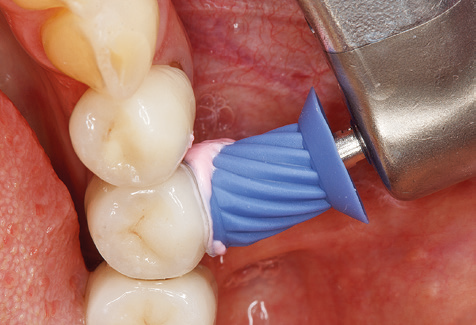

Die gute Ausleuchtung des Arbeitsfeldes stellt eine wesentliche Erleichterung dar. Bei dem von den Autoren genutzten System ist dies gelungen, indem ein 5­facher LED­Ring in das Handstück integriert wurde. Natürlich werden für dieses System unterschiedliche Arbeitsspitzen für die jeweiligen Indikationsbereiche angeboten. Eine gerade, universell einsetzbare Spitze ist das Basisinstrument zur maschinellen Instrumentierung natürlicher Zähne (Abb. 5a und b). Für schwer zugängliche Bereiche im Seitenzahnbereich werden gebogene Spitzen angeboten, die auch einen Zugang zu freiliegenden Furkationen ermöglichen (Abb. 6).

Abb. 4: Für das Sondieren an dentalen Implantaten sind biegsame, millimeterskalierte Sonden empfehlenswert (z.B. Colorvue Kit PCV11KIT6, Hu-Friedy). – Abb. 5a und b: Eine gerade Arbeitsspitze (1P, W&H Dentalwerk Bürmoos GmbH) ist universell für die Instrumentierung natürlicher Zähne geeignet. – Abb. 6: Für die Bearbeitung schwer zugänglicher Bereiche der Zahn- und Wurzeloberflächen (z.B. Furkationen) bieten sich gebogene Arbeitsspitzen (3Pr/3Pl, W&H Dentalwerk Bürmoos GmbH) an. – Abb. 7: Die spitz zulaufende sechseckige Implantatreinigungsspitze (1I, W&H Dentalwerk Bürmoos GmbH) ermöglicht eine atraumatische und effiziente Reinigung der Kronen- und Abutmentoberflächen. – Abb. 8: Für die manuelle Instrumentierung der Implantatoberflächen sind Titan- oder Carbonküretten geeignet.